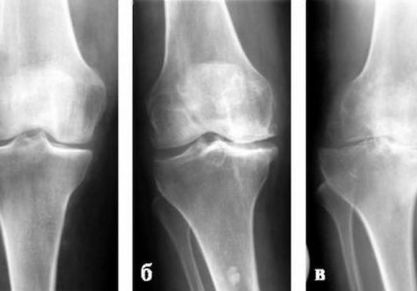

• Гонартроз — артроз коленного сустава. Чаще всего он встречается после 45 лет, хотя в последнее время заболевание «молодеет».